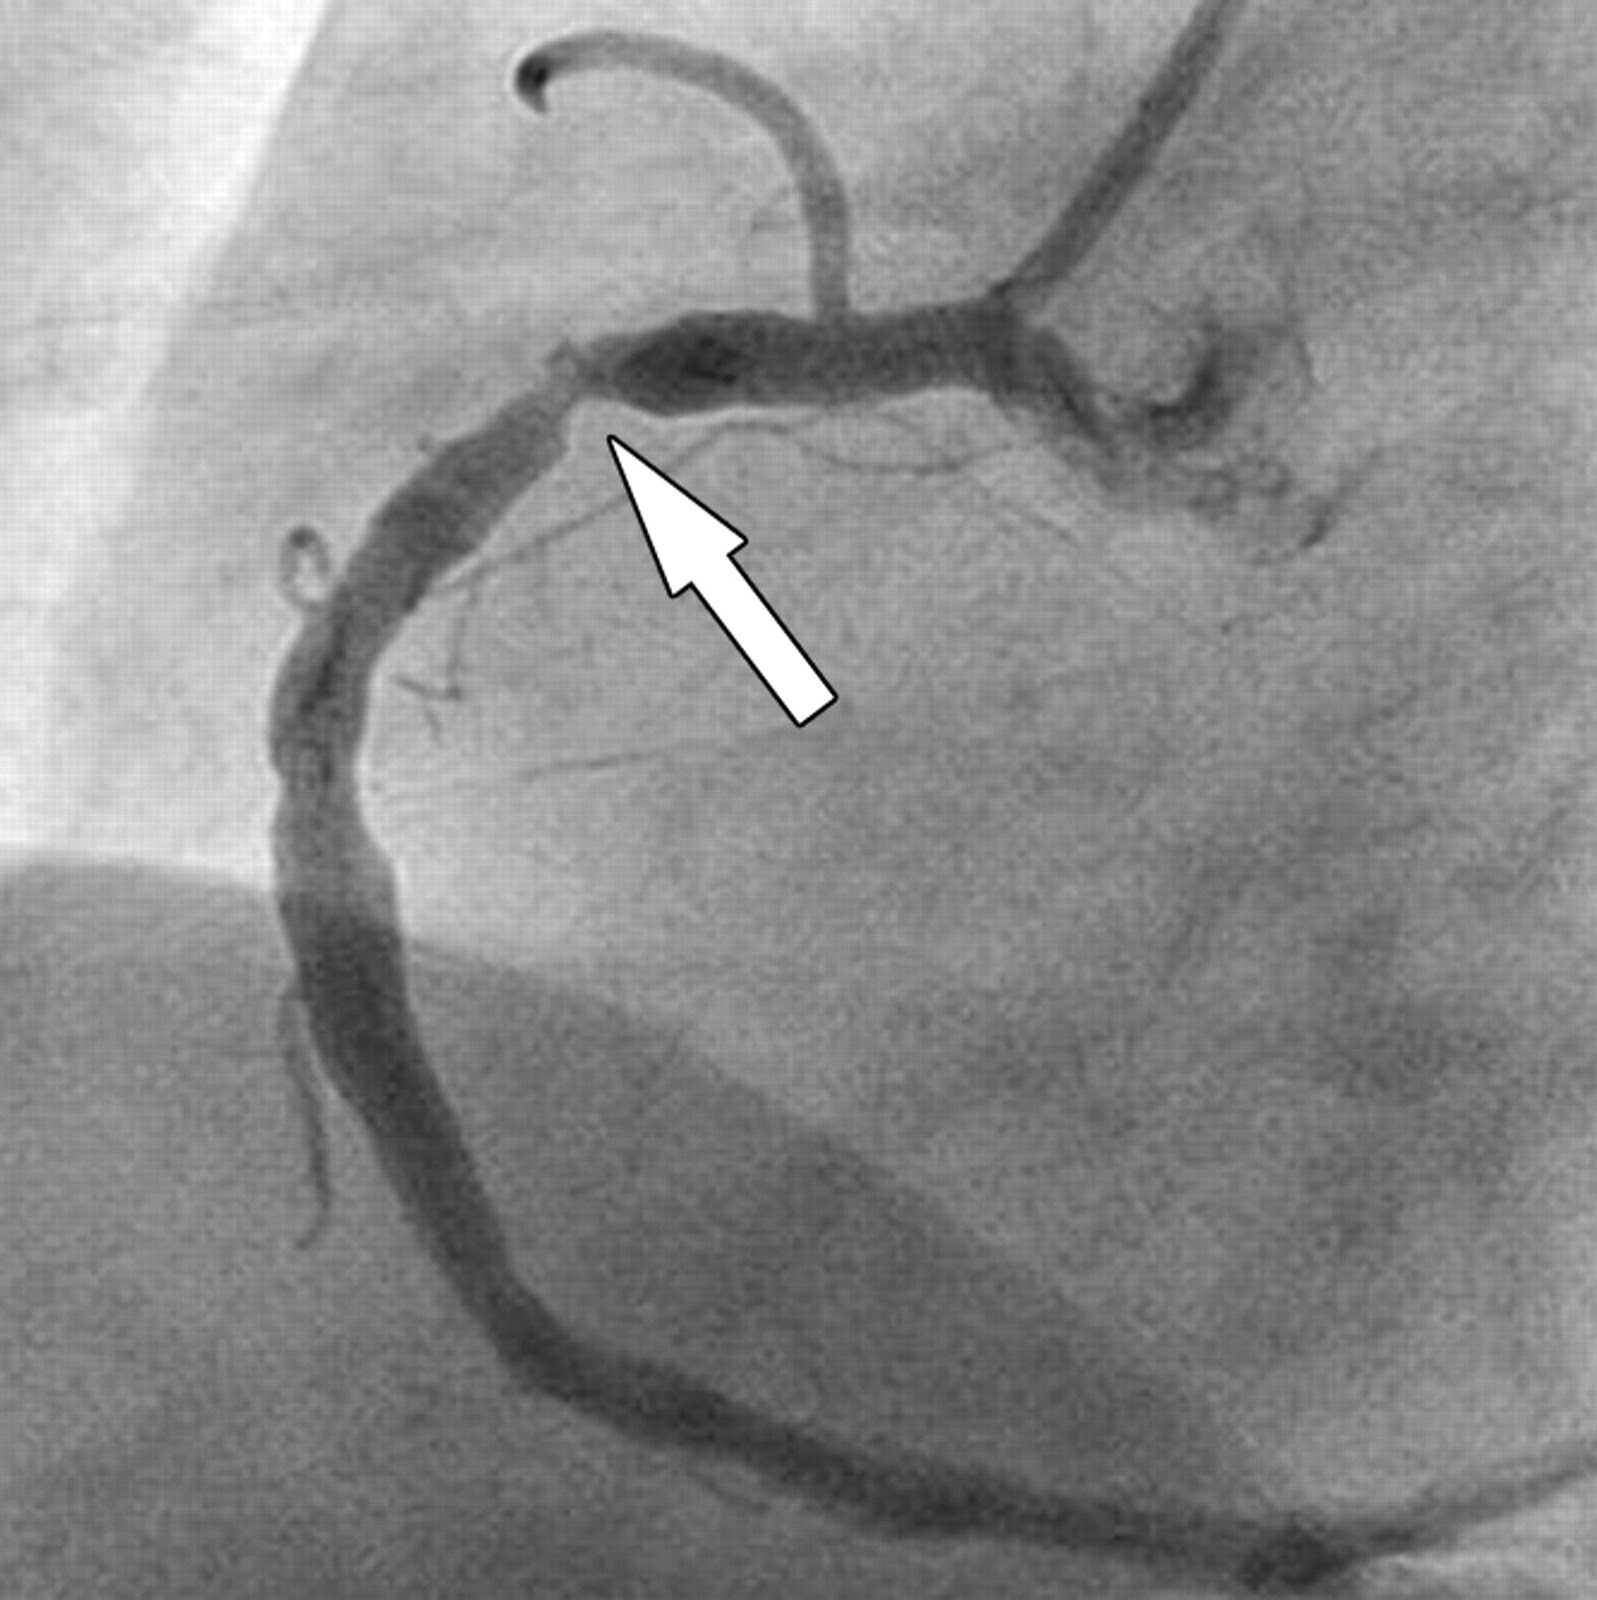

ESTENOSE CORONÁRIA